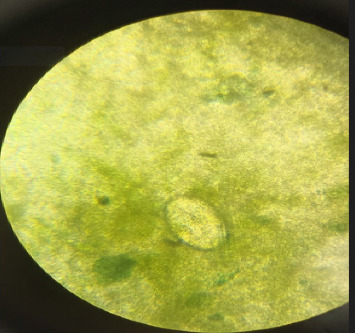

血吸虫病是由血吸虫属寄生虫感染引起的被忽视的热带病之一。血吸虫病累及大脑是感染的一种特别严重的表现。准确诊断和适当治疗脑血吸虫病至关重要,特别是在我们位于印度尼西亚偏远地区的卫生保健设施中,那里的可用资源非常有限。我们报告了一位31岁的女性患者,主诉强直阵挛性惊厥。在癫痫发作前,患者报告头痛6个月。患者对社会生活的记忆显示,她在一个种植园工作了15年;该种植园是蜗牛的自然栖息地,蜗牛是血吸虫的中间宿主。由于该地区诊断仪器的限制,未进行血清学检查。根据活检、粪便检查和CT扫描结果证实脑血吸虫病的诊断。患者入院时使用类固醇和吡喹酮联合用药,单次剂量为60mg /kg。她在14天后出院,总体健康状况令人满意。后续的CT扫描显示改善,证实了患者的临床恢复。本报告强调了与脑血吸虫病相关的诊断障碍,特别是在印度尼西亚的偏远地区和资源有限的环境中。尽管缺乏血清学检测,但通过放射成像、粪便显微镜检查和脑组织活检(组织病理学分析)成功地建立了明确的诊断,发现血吸虫卵周围有肉芽肿性炎症。患者表现为脑部占位性病变和神经系统症状,但未累及肝脏,使诊断不太直截了当。本病例说明了在流行地区出现脑病变的患者中,将脑血吸虫病作为鉴别诊断的重要性。当没有其他诊断工具(血清学检测)时,基于与放射成像、粪便显微镜检查和脑组织活检(组织病理学分析)相关的详细社会职业史来诊断脑血吸虫病是必不可少的。

Schistosomiasis is one of the neglected tropical diseases caused by parasitic worm infections of the genus Schistosoma. Involvement of the brain in schistosomiasis represents a particularly severe manifestation of the infection. Accurate diagnosis and appropriate treatment of cerebral schistosomiasis are essential, especially in our healthcare facility located in a remote area of Indonesia, where available resources are highly limited. We reported a 31-year-old female patient complaining of tonic-clonic convulsions. Before experiencing seizures, the patient reported experiencing headaches for 6 months. The patient's anamnesis regarding her social life revealed that she has been employed on a plantation for 15 years; the plantation serves as a natural habitat for snails, intermediate hosts for Schistosoma sp. Serological examinations were not performed due to the constraints of diagnostic instruments in the region. Cerebral schistosomiasis diagnosis was verified based on biopsy, stool examination, and CT scan results. She was admitted with a combination of steroids and praziquantel at a dosage of 60 mg/kg single dose. She was released after 14 days in satisfactory overall health. The follow-up CT scan revealed improvement, corroborated by the patient's clinical recovery. This report emphasizes the diagnostic obstacles associated with cerebral schistosomiasis, particularly in remote regions and resource-limited settings in Indonesia. Despite the absence of serological testing, a definitive diagnosis was successfully established through radiological imaging, stool microscopic examination, and brain tissue biopsy (histopathological analysis) which revealed Schistosoma eggs surrounded by granulomatous inflammation. The patient presented with space-occupying brain lesions and neurological symptoms, but without hepatic involvement, making the diagnosis less straightforward. This case illustrates the significance of recognizing cerebral schistosomiasis as a differential diagnosis in patients presenting cerebral lesions in endemic locations. Diagnosis of cerebral schistosomiasis based on a detailed social occupational history correlated with radiological imaging, stool microscopic examination, and brain tissue biopsy (histopathological analysis) is essential when other diagnostic tools (serological testing) are unavailable.